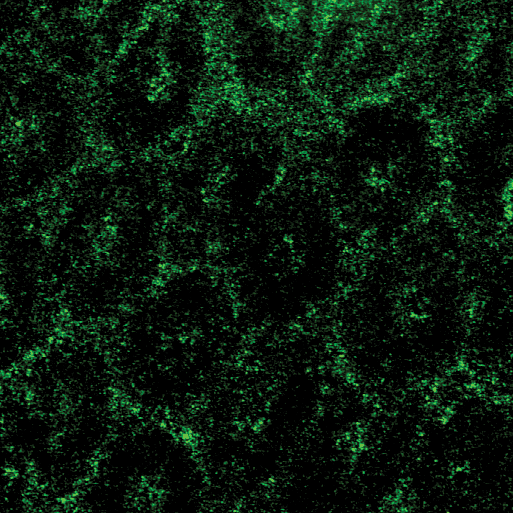

Performing their experiments in mice, the team tested the effects of polymers, which include dietary fiber as well as therapeutics such as medicines for constipation. The researchers fed some mice a diet rich in polymers and others (the controls) a polymer-free diet. Using a technique called confocal reflectance microscopy they measured the thickness of the gut gel and the degree to which the gel was compressed as a result of the consumed polymers. Mice given a high-polymer diet, they found, had a more compressed gel layer.

The researchers also found that dietary fiber and gut bacteria—which are part of a community of microorganisms collectively known as gut microbiota—can work together to influence how the gut gel changes shape. They performed the same polymer/fiber experiments in germ-free mice, which are mice carefully raised to not have any bacteria in their gut. The results showed that the polymers compressed the gut gels of these germ-free mice to a greater degree. This implies that species of bacteria in our gut that are known to break down polymers can weaken the compressing effect.

"We previously thought of the gel as a static structure, so it was unexpected to find an interplay between diet and gut microbiota that rapidly and dynamically changes the biological structures that protect a host," says Ismagilov.